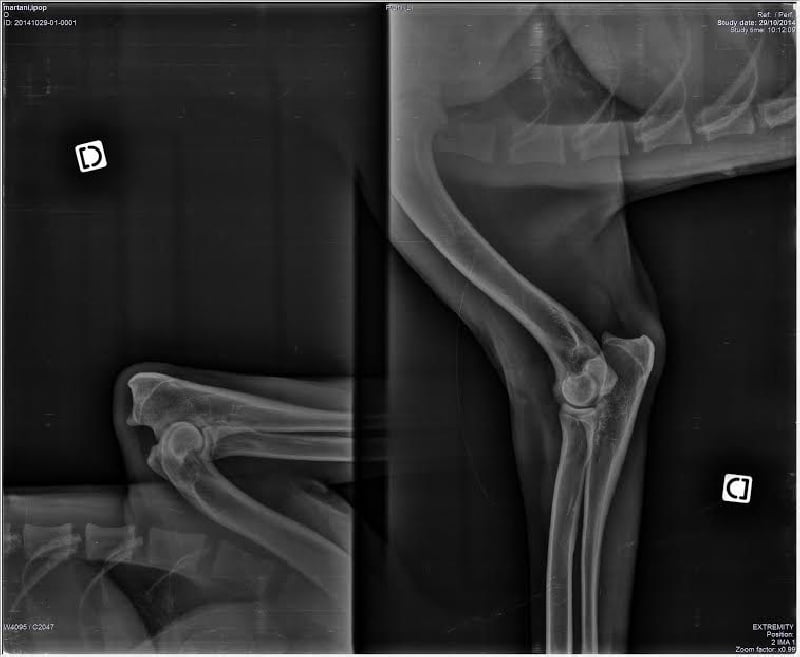

SCAU : Mention TRES BIEN radios des coudes : HD/A radios des hanches : HD/A |